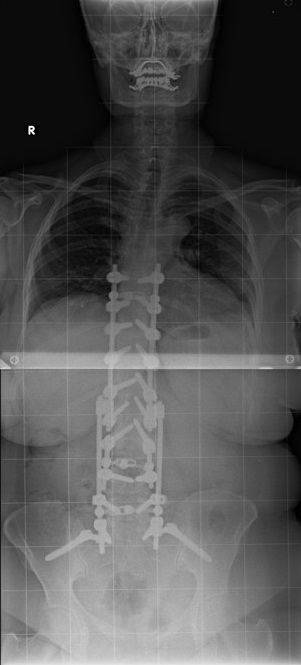

60 Yaşında Kadın Hasta

Ameliyat Öncesi